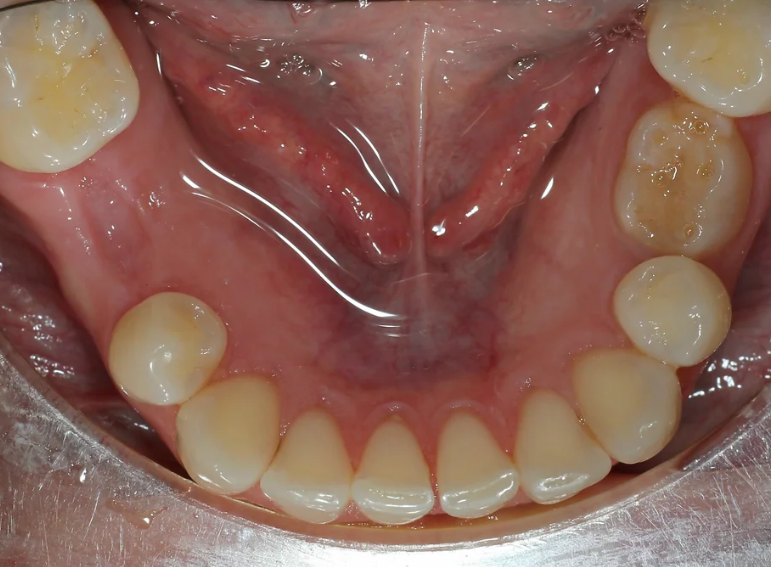

Missing lower premolar due to hypodontia replaced with an implant.